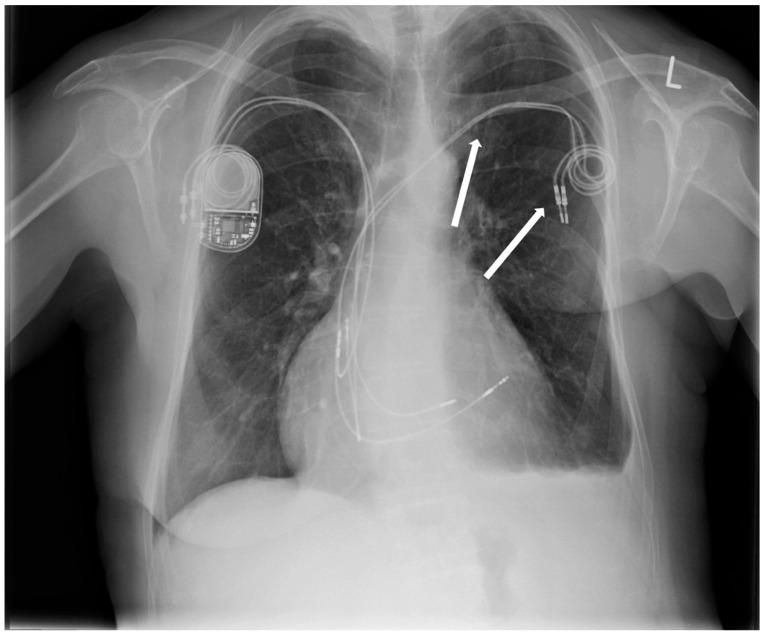

Cardiological and oncological patients comprise the majority of patients admitted to the emergency unit with chronic or acute conditions that are the dominant cause of death worldwide. However, electrotherapy and implantable devices (pacemakers and cardioverters) improve the prognosis of cardiological patients. We present the case report of a patient who, in the past, had a pacemaker implanted due to symptomatic sick sinus syndrome (SSS) without removing the two remaining leads. Echocardiography revealed severe tricuspid valve regurgitation. The tricuspid valve septal cusp was in a restricting position due to the two ventricular leads passing through the valve. A few years later, she was diagnosed with breast cancer. We present a 65-year-old female admitted to the department due to right ventricular failure. The patient manifested symptoms of right heart failure, predominated by ascites and lower extremity edema, despite increasing doses of diuretics. The patient underwent a mastectomy two years ago due to breast cancer and was qualified for thorax radiotherapy. A new pacemaker system was implanted in the right subclavian area as the pacemaker generator occupied the radiotherapy field. In the case of right ventricular lead removal and the need for pacing and resynchronization therapy, guidelines allow a coronary sinus for LV pacing to avoid passing the leads through the tricuspid valve. We facilitated this approach in our patient, suggesting that the percentage of ventricular pacing was very low.

心脏病患者和肿瘤患者占因慢性或急性疾病入住急诊科患者的大多数,这些疾病是全球主要的死亡原因。然而,电疗法和植入式设备(起搏器和心脏复律器)可改善心脏病患者的预后。我们报告一例患者,该患者过去因症状性病态窦房结综合征(SSS)植入了起搏器,但未取出剩余的两根导线。超声心动图显示严重三尖瓣反流。由于两根心室导线穿过瓣膜,三尖瓣隔叶处于受限位置。几年后,她被诊断出患有乳腺癌。我们介绍一名65岁女性因右心室衰竭入住该科室。尽管利尿剂剂量不断增加,但患者仍表现出以腹水和下肢水肿为主的右心衰竭症状。该患者两年前因乳腺癌接受了乳房切除术,并符合胸部放疗条件。由于起搏器发生器占据放疗区域,在右锁骨下区域植入了新的起搏器系统。在需要移除右心室导线并进行起搏和再同步治疗的情况下,指南允许通过冠状窦进行左心室起搏,以避免导线穿过三尖瓣。我们在患者中采用了这种方法,表明心室起搏的百分比非常低。